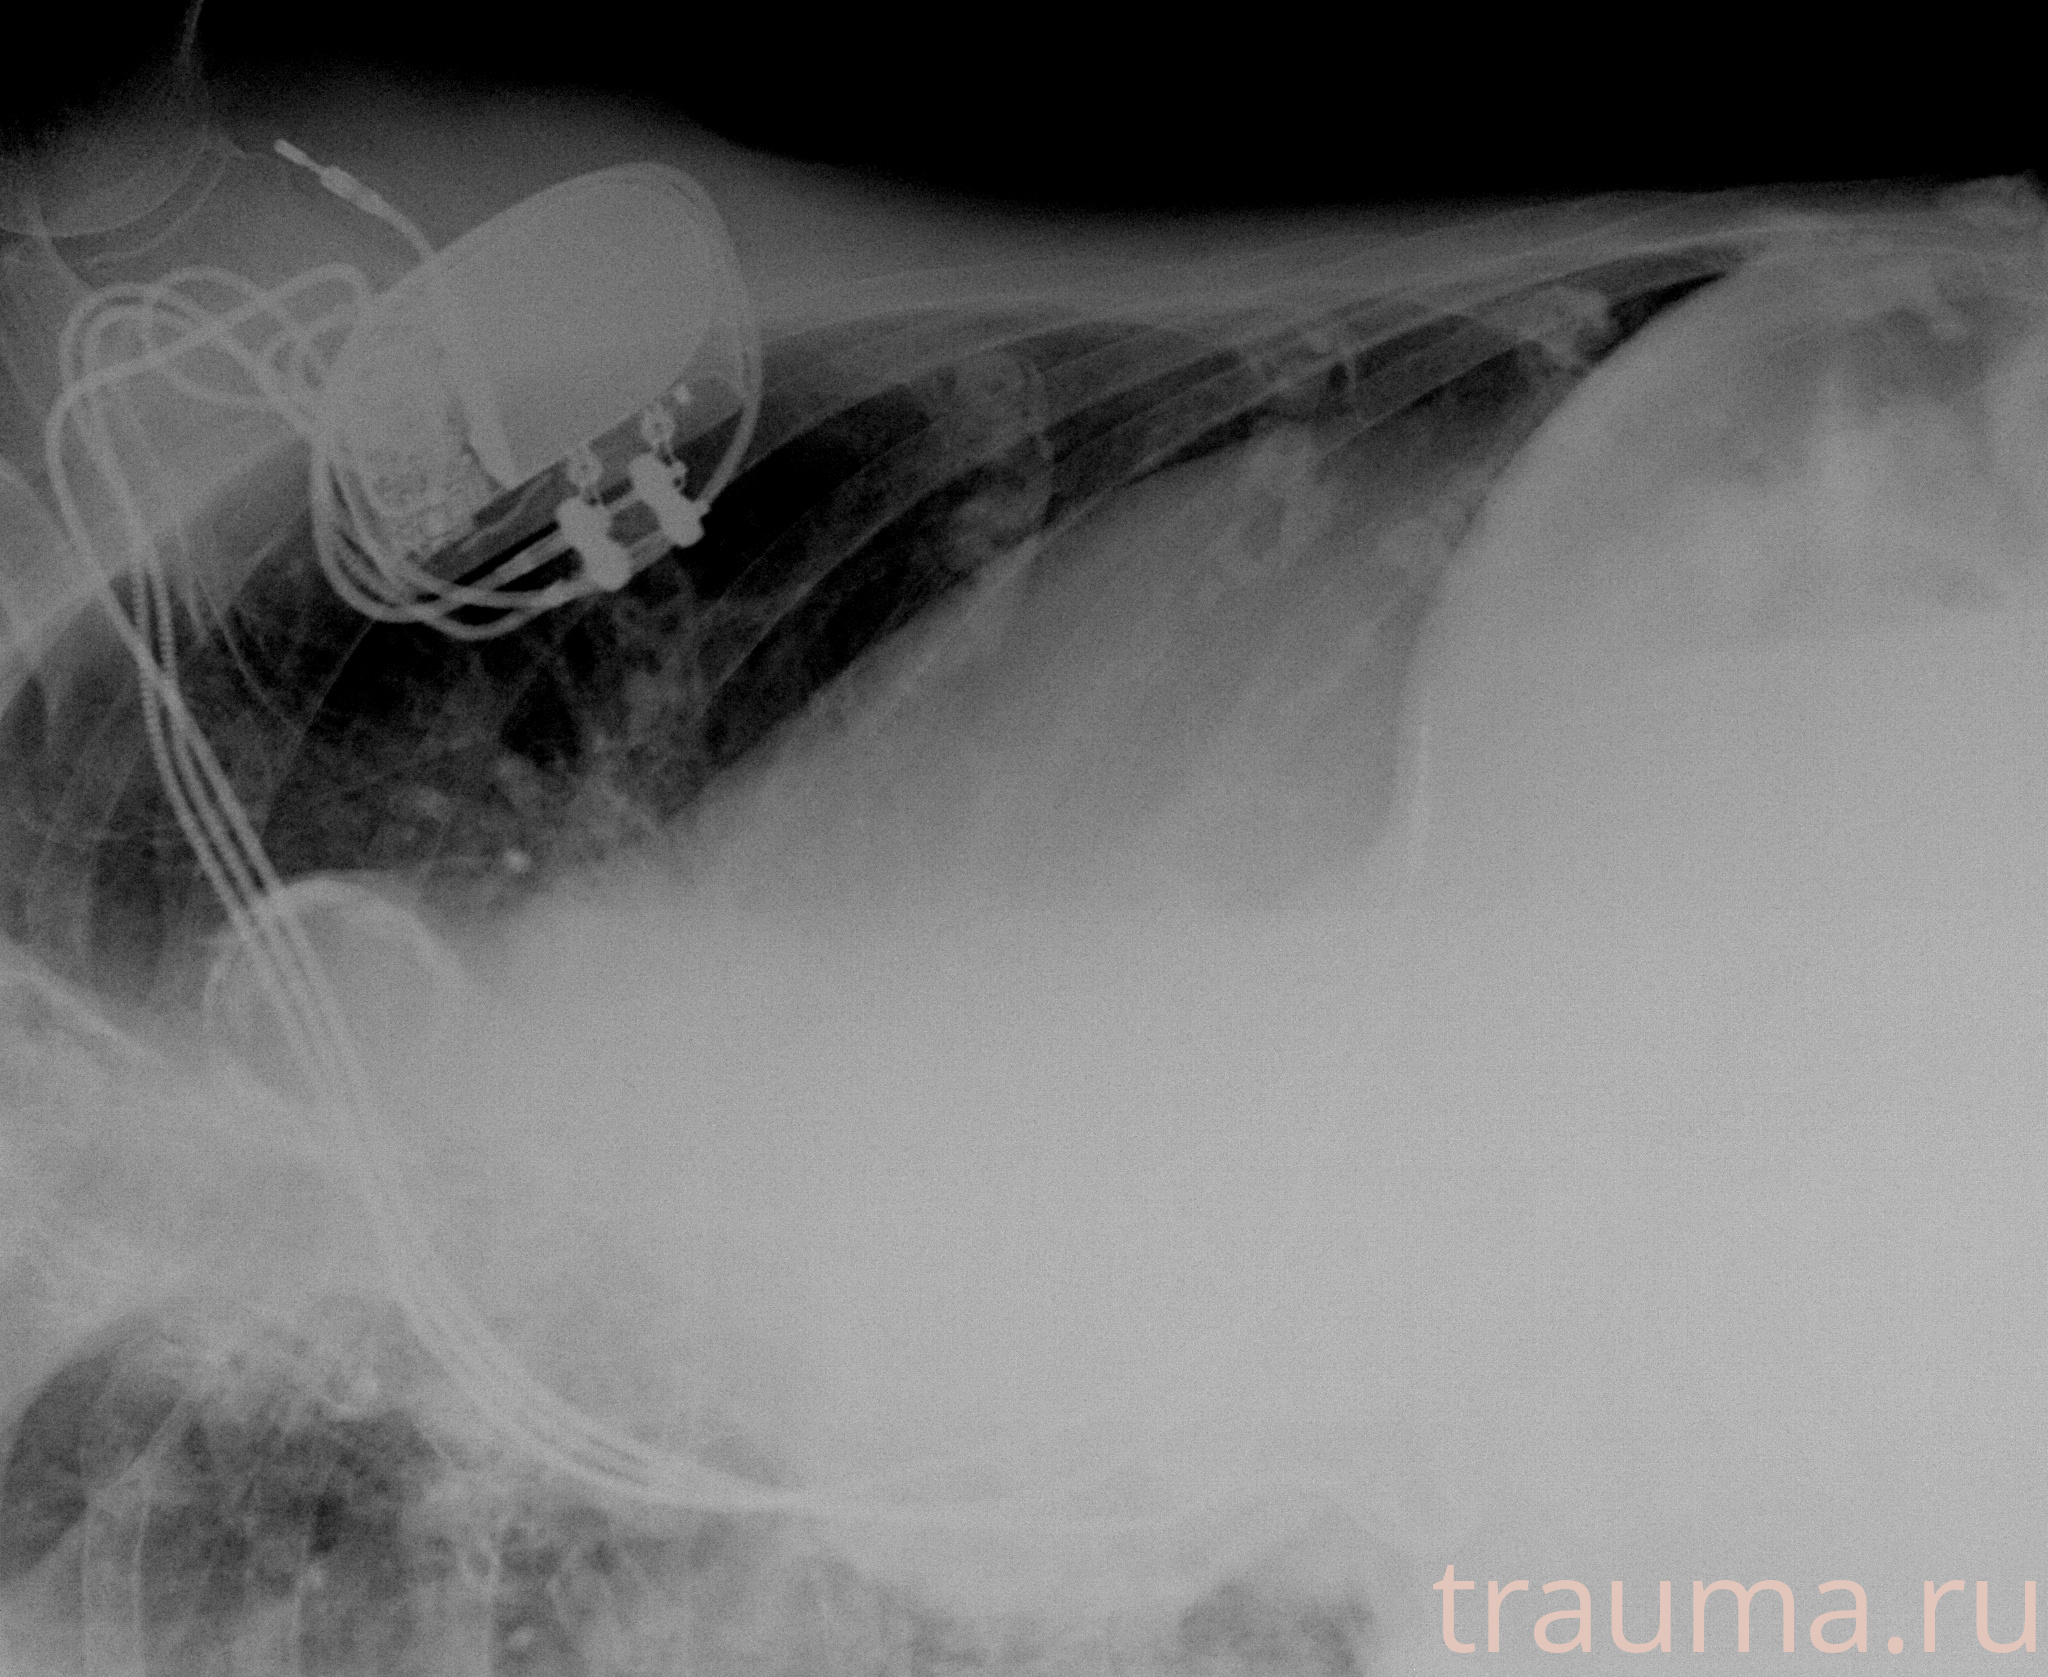

Рентгенограммы

Рентген на дому: по вашему адресу приезжает врач-рентгенолог, травматолог-ортопед с мобильным рентгеновским аппаратом, проводит диагностику травмы или заболевания, делает необходимые рентгенограммы, дает рекомендации по дальнейшему лечению. Получить качественные снимки в домашних условиях возможно благодаря уникальной методике, разработанной МосРентген Центром для института  Склифосовского

при переломе шейки бедра и пневмонии от компании МосРентген Центр - партнера Института имени Склифосовского